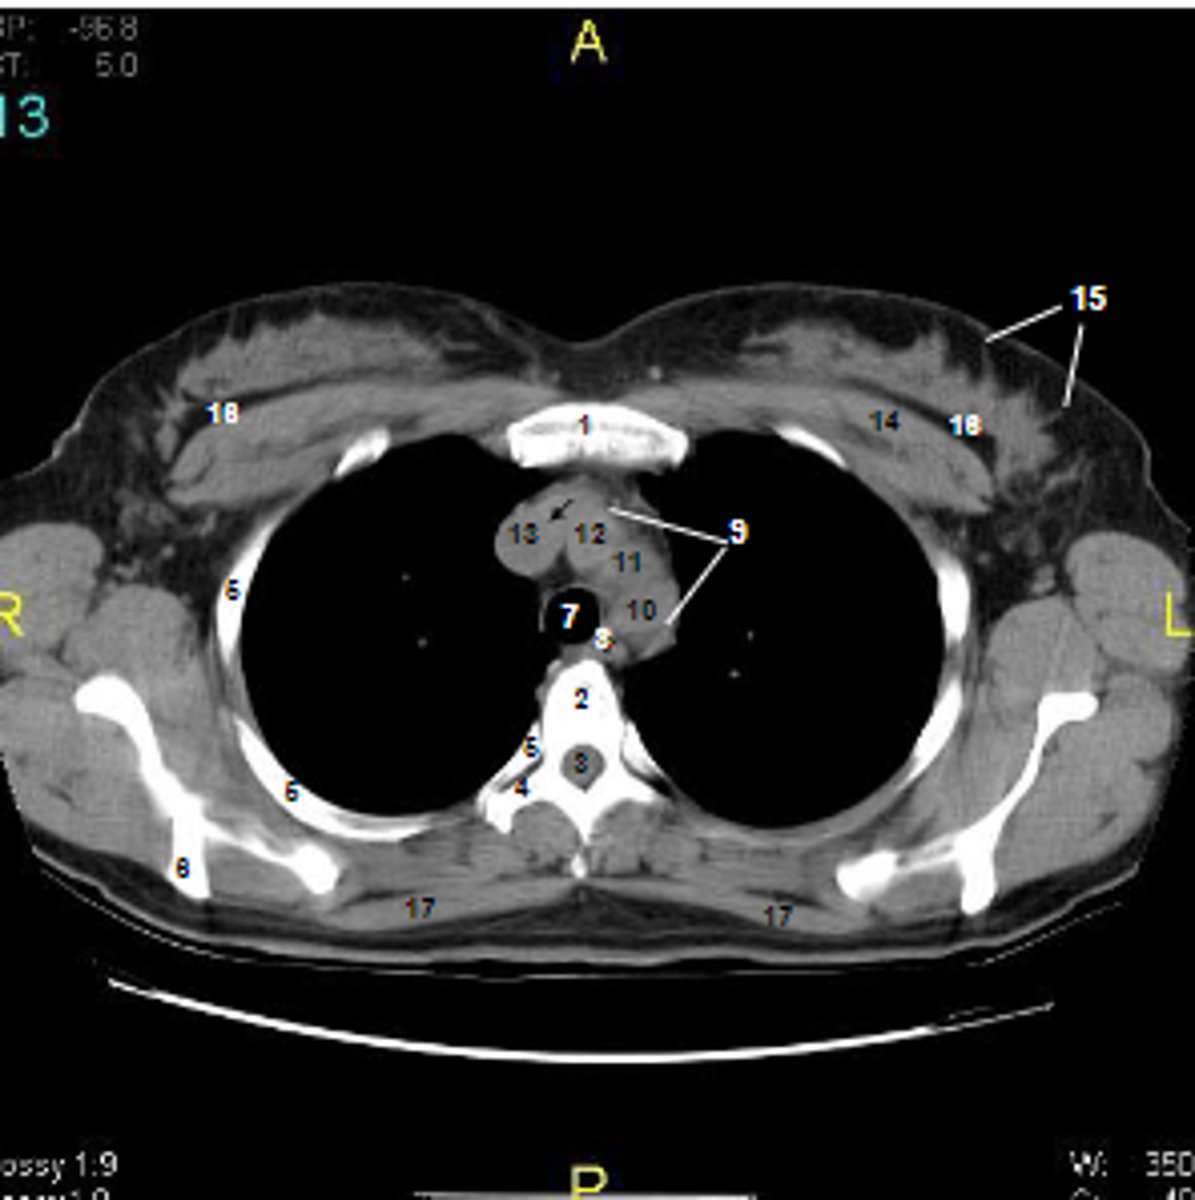

1

at what number is the sternum

2

at what number is the vertebral body

3

at what number is the vertebral canal/ spinal cord

4

at what number is the transverse process of vertebra

5

at what number is the rib

6

at what number is the spine of scapula

7

at what number is the trachea

8

at what number is the esophagus

9

at what number is the arch of aorta

10

at what number is the left subclavian artery

11

at what number is the common carotid artery

12

at what number is the brachiocephalic trunk

13

at what number is the superior vena cava

14

at what number is pectoralis major

15

at what number are Cooper's ligaments

16

at what number is the retromammary space

17

at what number is trapezius